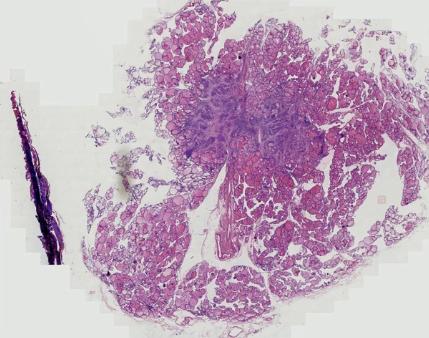

为了进一步确诊疾病,又为她安排了成像准确率更高的 四维弹性成像检查。

结果显示佟女士的 甲状腺体积增大,包膜欠完整 ,双侧叶可见多个囊实性及等回声结节,边界欠清,部分结节相互融合。

右侧叶最大者 23mm*16mm ,左侧叶最大者 39mm*23cm , TI-RADS 3类,弹性评分2分,良性结节的可能性比较大。